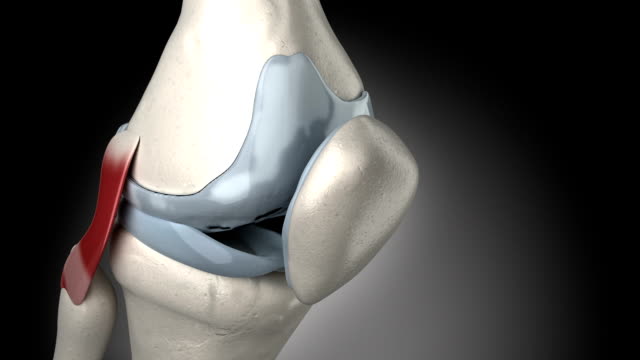

무릎 연골판 손상은 크게 두 가지 원인으로 나눌 수 있습니다.

무릎 연골판 손상의 주요 증상은 다음과 같습니다.

- 무릎 관절에서 통증 및 불편함

- 관절의 불안정성

- 팽팽한 무릎 관절

- 붓기 및 염증